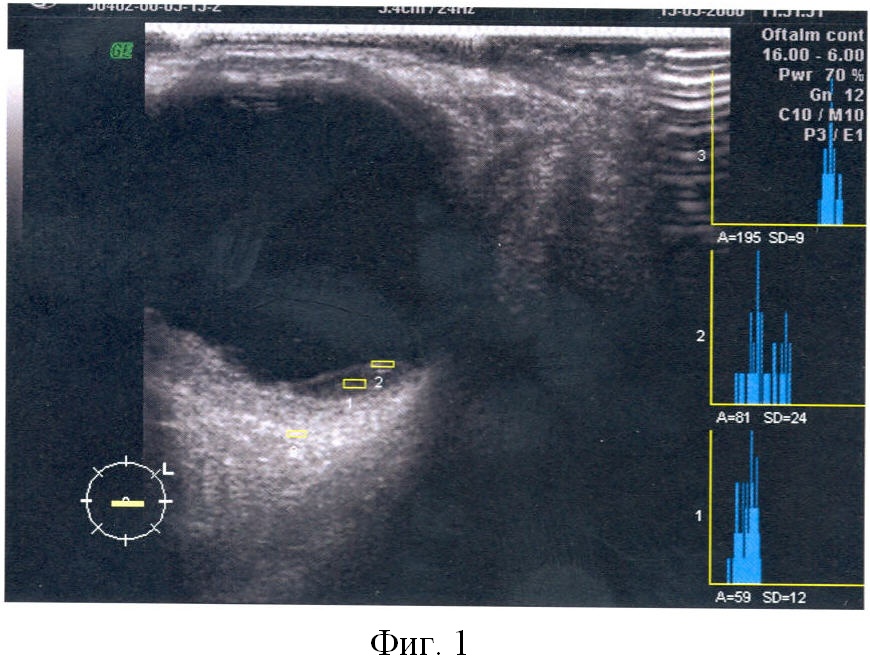

На фигуре 4 показано двухмерное сканирование субретинальной неоваскулярной мембраны с определением показателей плотности патологического очага в двухмерном режиме.

А1 – 178;

А2 – 197;

А3 – 212;

K2D=(A1+A2)/A3=1,76;

K2D=1,76.